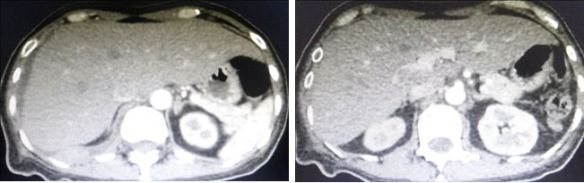

ST is a 62-year-old man from Perak. Two years ago (May 2018) he was diagnosed with cancer of the appendix and adjacent caecum.

A CT scan of the chest, abdomen and pelvis did not show the cancer had spread to other parts of the body.

In March 2020, ST started to have abdominal pain and at times, he vomited. He went back to the same hospital where he had his surgery. A CT scan was done and revealed:

• Acute small bowel obstruction with no evidence of tumour recurrence.

• Liver lesions – cyst or metastasis ?

• Bilateral small renal cyst.

A CT scan done on 4 August 2020 showed:

• Progression of disease evidenced by increased number and size of cystic liver lesions – likely metastasis.

• No evidence of recurrence.

• Prostatomegaly.